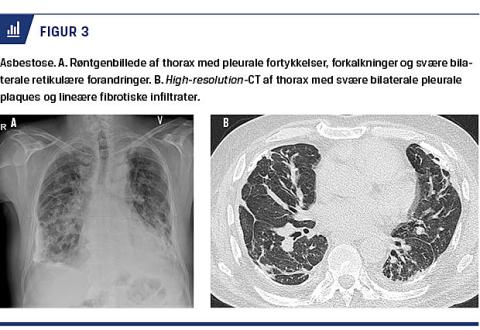

I Helsinkikriteri-erne anbefaler man som førstevalg røntgenoptagelse af thorax med anvendelse af Inter-national Labour Orga-nizations klassifikationssystem til vurdering af diagnosen og brug af CT i tvivlstilfælde [10, 12]. Røntgenop-tagelser af thorax viser normale forhold hos 10-18% af personer med asbestose [9]. Desuden er CT og især high-resolution (HR)-CT mere specifik og sensitiv end røntgenoptagelse [7] og anbefales som førstevalg af Dansk Lungemedicinsk Selskab [2]. Figur 3 viser typiske eksempler på røntgenoptagelse og HRCT. HRCT er især værdifuld: 1) til identifikation af tidlige stadier af asbestose, 2) ved fund af grænsetilfælde af lungefibrose ved almindelig røntgenoptagelse af thorax, 3) ved fund af normale forhold på røntgenoptagelse af thorax, men lungefunktion med et restriktivt billede, 4) ved udbredte pleurale forandringer, der slører lungeparenkymet på et røntgenbillede, og 5) ved mistanke om interstitiel lungesygdom [10, 14]. Ved tolkning af CT-billeder benyttes international classification of HRCT for occupational and environmental diseases [15]. Det er en særlig diagnostisk udfordring, når billedet ligner idiopatisk pulmonal fibrose, men der samtidig er pleurale plaques, eller omfanget af asbesteksponeringen er usikkert. Patienterne bør ud over udredning på en arbejdsmedicinsk klinik og på en lungeafdeling også drøftes på en tværfaglig konference mhp. at stille en endelig diagnose. Lungefunktionsun-dersøgel-ser bør omfatte måling af forceret ekspiratorisk volumen i første sekund, FVC, statiske lungevolumina (TLC og residualvolumen) samt måling af DLCO [7].